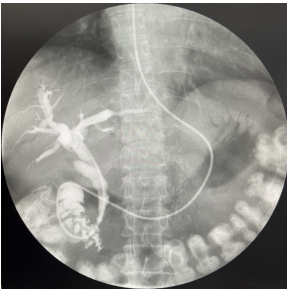

術(shù)后鼻膽管造影顯示膽管通暢,未見結(jié)石殘留

術(shù)后患者腹痛緩解,未再發(fā)熱,黃疸逐漸好轉(zhuǎn),2天后剪斷鼻膽管,繼續(xù)膽道支架,通暢膽道內(nèi)引流,控制感染后出院。